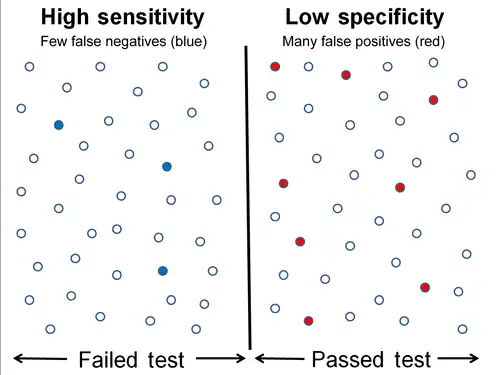

High sensitivity and low specificity

High sensitivity and low specificity -

Low sensitivity and high specificity

Low sensitivity and high specificity

The middle solid line in both figures above that show the level of sensitivity and specificity is the test cutoff point. As previously described, moving this line results in a trade-off between the level of sensitivity and specificity. The left-hand side of this line contains the data points that tests below the cut off point and are considered negative (the blue dots indicate the False Negatives (FN), the white dots True Negatives (TN)). The right-hand side of the line shows the data points that tests above the cut off point and are considered positive (red dots indicate False Positives (FP)). Each side contains 40 data points.

For the figure that shows high sensitivity and low specificity, there are 3 FN and 8 FP. Using the fact that positive results = true positives (TP) + FP, we get TP = positive results - FP, or TP = 40 - 8 = 32. The number of sick people in the data set is equal to TP + FN, or 32 + 3 = 35. The sensitivity is therefore 32 / 35 = 91.4%. Using the same method, we get TN = 40 - 3 = 37, and the number of healthy people 37 + 8 = 45, which results in a specificity of 37 / 45 = 82.2 %.

For the figure that shows low sensitivity and high specificity, there are 8 FN and 3 FP. Using the same method as the previous figure, we get TP = 40 - 3 = 37. The number of sick people is 37 + 8 = 45, which gives a sensitivity of 37 / 45 = 82.2 %. There are 40 - 8 = 32 TN. The specificity therefore comes out to 32 / 35 = 91.4%.